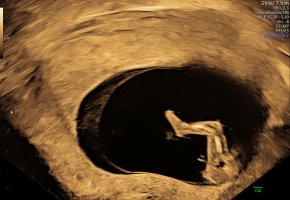

Tror jeg ville tippa gutt jeg! Synes nuben (om det er den vi ser) peker noe oppover sammenlignet med ryggen. Men vanskelig å siKan dere se noe her?

Jeg ser for meg det er jente![]()

Fikk «slightly leaning boy» fra admin på fb gruppe. Må jo være nuben vi ser daTror jeg ville tippa gutt jeg! Synes nuben (om det er den vi ser) peker noe oppover sammenlignet med ryggen. Men vanskelig å si![]()

Ja, det er nok det da! SpennendeFikk «slightly leaning boy» fra admin på fb gruppe. Må jo være nuben vi ser da![]()